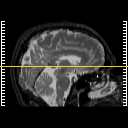

Click on sagittal image to select slice. Click on thin tickmark to change timepoint, or thick tickmark for overlay.